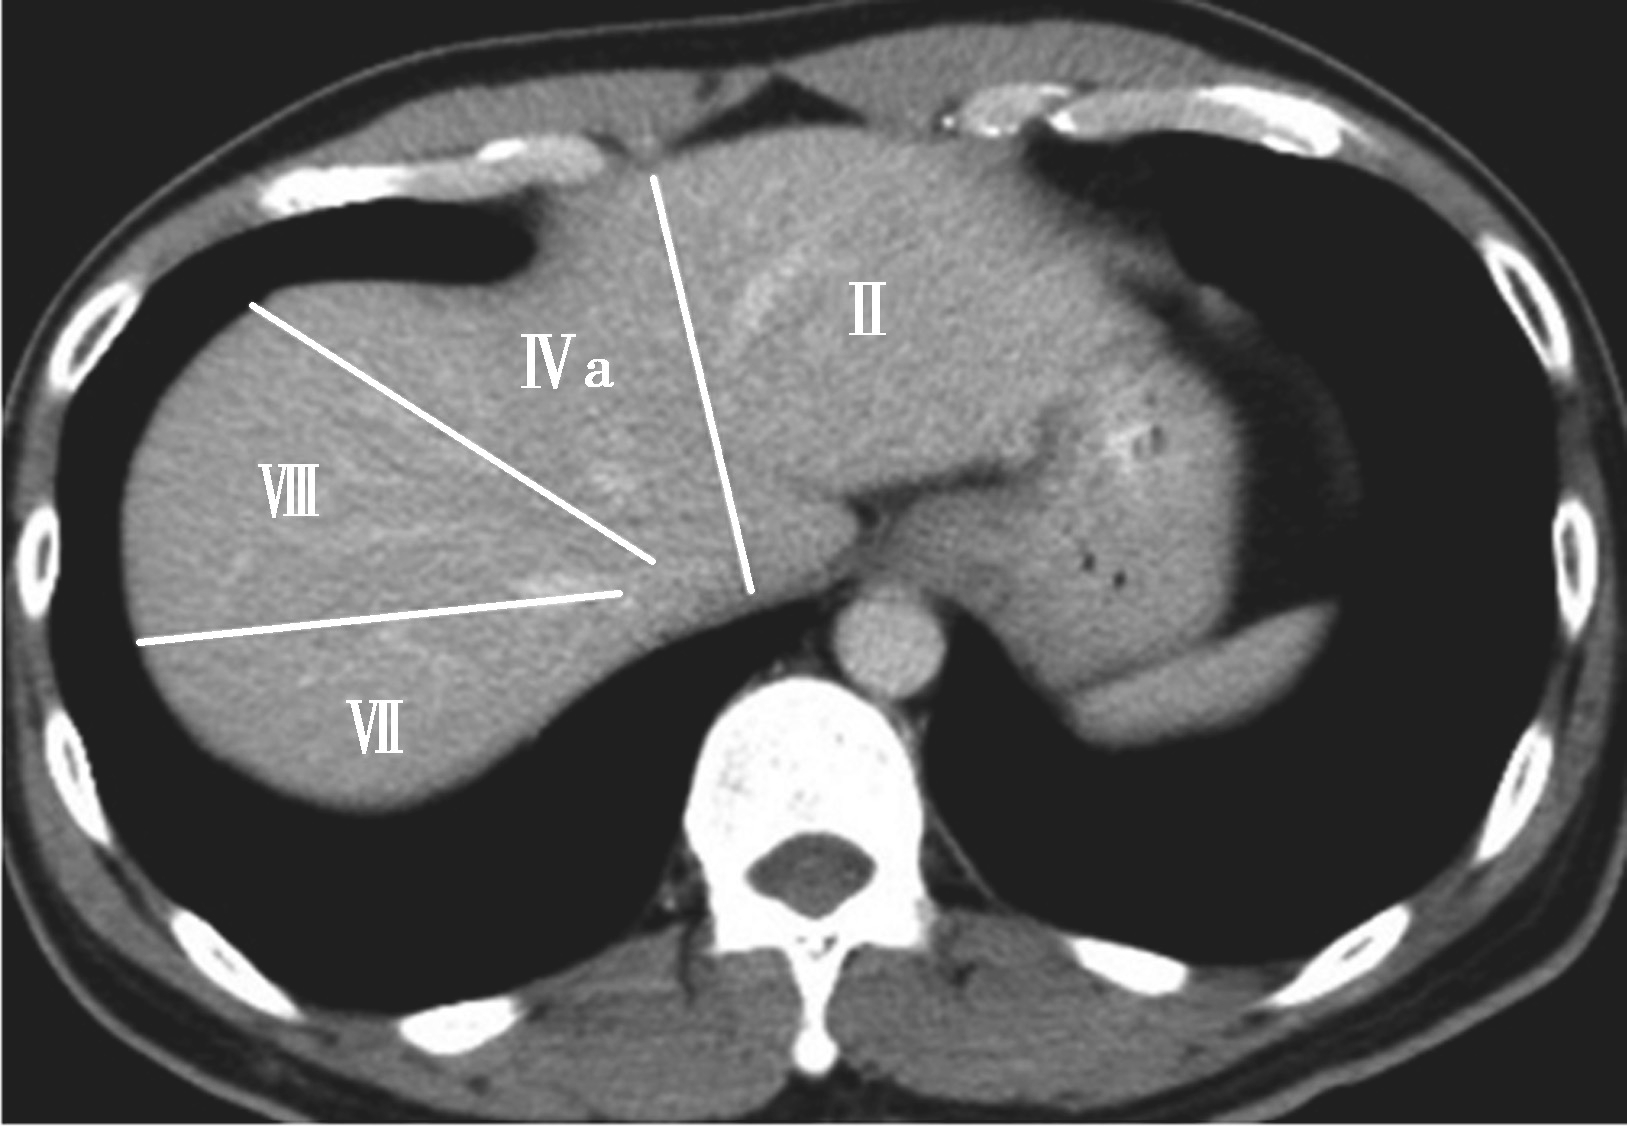

(3)肝8段划分法(图5-21-35):

Couinaud根据门静脉及肝静脉的分布将肝脏分为8段,门静脉分布于肝段内,肝静脉分布于肝段间。8分段法是临床外科和影像最为常用的分段法。以肝中静脉为界分为左、右半肝;以肝左静脉为界将左半肝分为左内(Ⅳ段)和左外叶(Ⅱ段+Ⅲ段);左外叶以门静脉左支为界水平分为上(Ⅱ段)下(Ⅲ段)两段;以肝右静脉为界分右半肝为前叶(Ⅷ段+Ⅴ段)和后叶(Ⅵ段+Ⅶ段);以门静脉右支为界将右肝横向分为上下两段分别为右前上段(Ⅷ段)、右前下段(Ⅴ段),右后下段(Ⅵ)和右后上段(Ⅶ段);肝尾状叶为单独一段(Ⅰ段)。

图5-21-35 肝8段划分法示意图